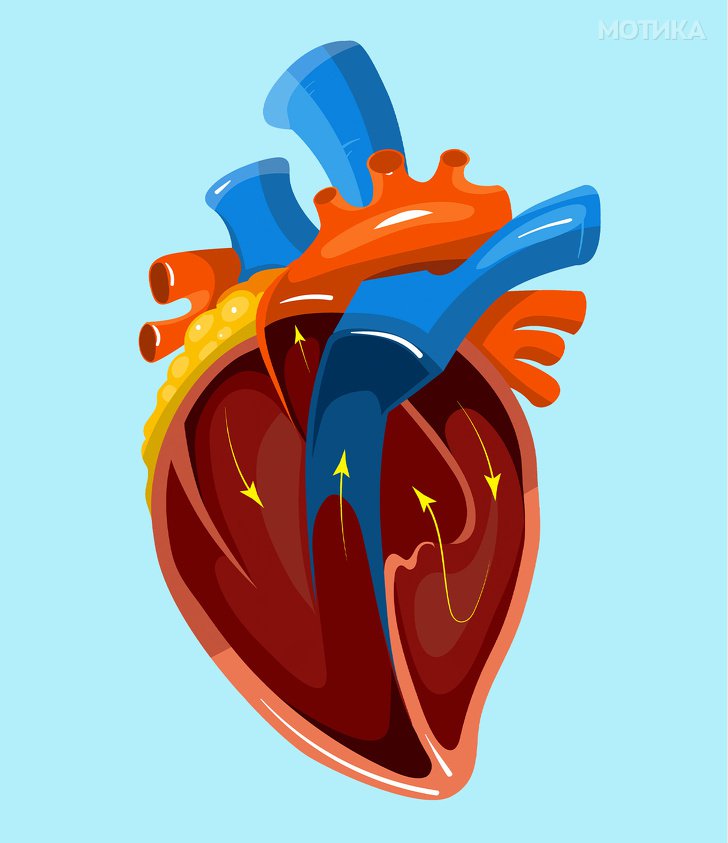

1. Срце

- Срцето создава доволно притисок за да ја исфрли крвта 9 метри во воздухот, што е речиси исто толку високо колку и просечната 3-катна зграда.

- Во просек женското срце чука побрзо од машкото.

- Секој ден пумпа околу 7.500 литри крв.